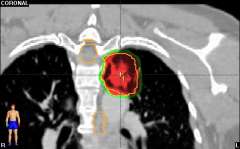

Stereotactic body radiation therapy (SBRT) is a treatment procedure similar to central nervous system (CNS) stereotactic radiosurgery, except that it deals with tumors outside of the CNS. A stereotactic radiation treatment for the body means that a specially designed coordinate-system is used for the exact localization of the tumors in the body (Figure 1) in order to treat it with limited but highly precise treatment fields. SBRT involves the delivery of a single high dose radiation treatment or a few fractionated radiation treatments (usually up to five treatments). A high potent biological dose of radiation is delivered to the tumor, improving the cure rates for the tumor, in a manner previously not achievable by standard conventional radiation therapy (Figure 2).

Similarly, because this specialized form of radiation involves the use of multiple radiation beam angles, expert radiation oncologists specialized in this technique are able to safely deliver high doses of radiation, with very sharp dose gradient outside the tumor and into the surrounding normal tissue (Figure 3).